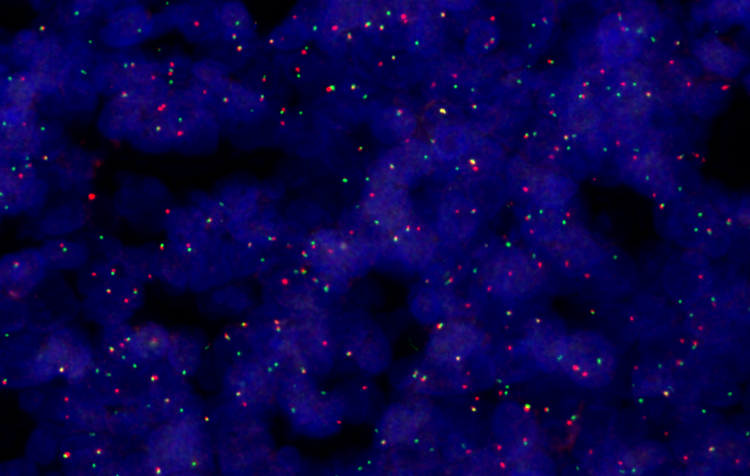

FISH analysis, 40X

Supporting up to six high-performance X Line™ objectives and featuring True Color LED illumination and color-corrected camera profiles, the SLIDEVIEW VS200 system delivers clarity in whole slide images. The scanner is engineered for consistent reproduction of sample and stain characteristics, minimizing the need for rescans and supporting efficient diagnoses.

Discover more details in your samples with five imaging modes—brightfield, polarization, fluorescence, darkfield, and phase contrast—and the ability to combine multiple techniques in a single scan. This flexibility offers a wide range of possibilities to observe histology and cytology samples, from routine pathology to complex molecular characterization of cancerous tissue.

The scanner you need now, with the flexibility to expand as your lab’s priorities evolve. Whether you need to capture multiplexed fluorescence for cancer signature discovery, use polarized light to elucidate amyloids in brain tissue, or analyze large format samples for histological features, the SLIDEVIEW VS200 scanner can be adapted to solve the challenge.